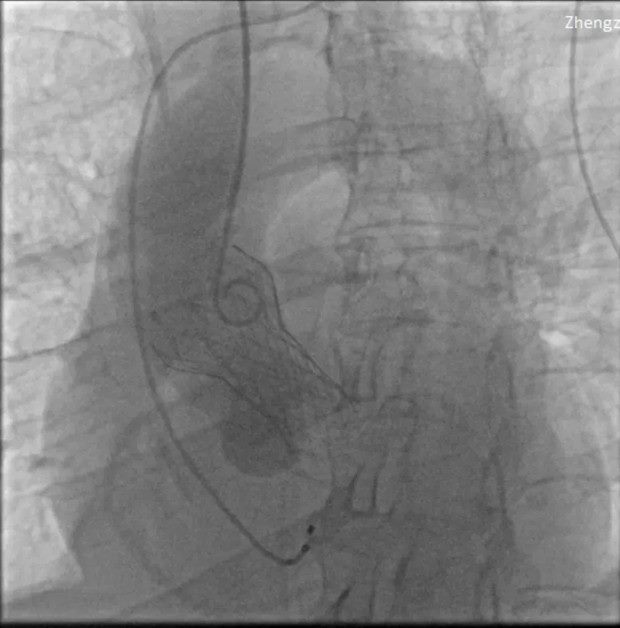

▲TAVR术后影像

TAVR手术的成功离不开先进的医疗技术和设备支持,以及医护团队的协作。团队利用高精度影像设备进行术前评估,术中实时监控,确保导管和人工瓣膜的准确定位,并采用最新一代的人工瓣膜材料,具有更好的生物相容性和耐久性,减少术后并发症。TAVR的微创特点大大缩短了患者的术后恢复时间。